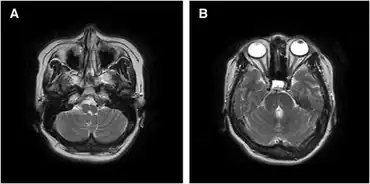

Hemiplegia is identified by clinical examination by a health professional, such as a physiotherapist or doctor. Radiological studies like a CT scan or magnetic resonance imaging of the brain should be used to confirm injury in the brain and spinal cord, but alone cannot be used to identify movement disorders. Individuals who develop seizures may undergo tests to determine where the focus of excess electrical activity is.[18]